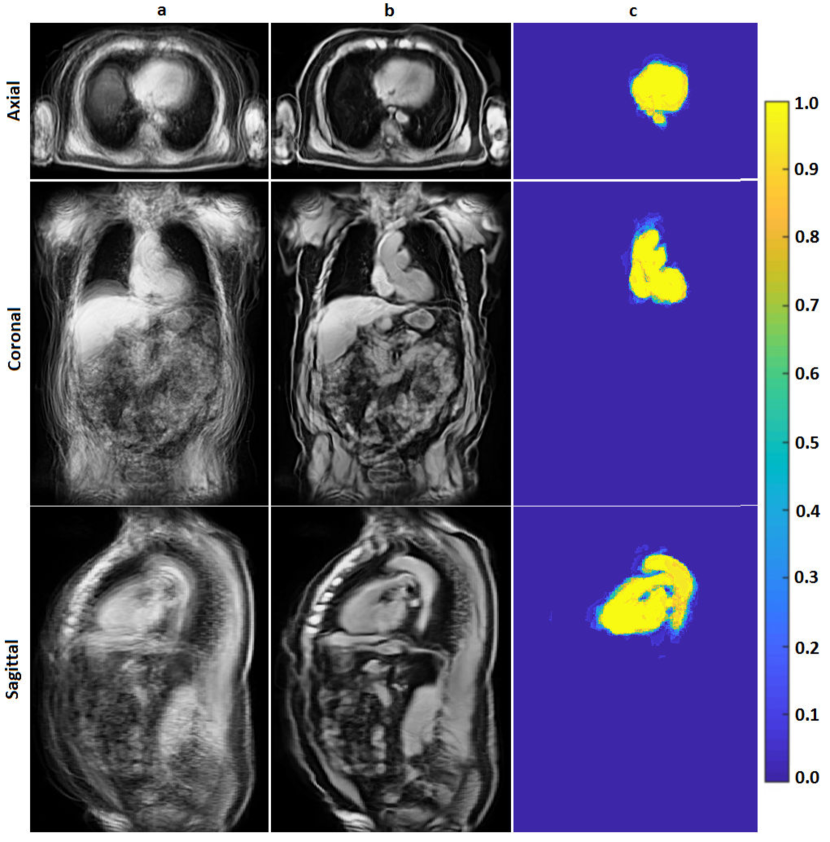

The classification priors of the samples could be estimated by any method such as the multiatlas registration or the hierarchical random forest classifier proposed in [Fallah 2018a, Fallah 2018b, Fallah 2019b, Fallah 2019a]. This happened when the classification probabilities estimated by those methods were not accurate enough to be considered as final classification probabilities (posteriors) rather as initial classification probabilities (priors). For example, the classification probabilities estimated by the proposed forest could not differentiate different kinds of cardiac adipose tissues on fat-water MR images. They could only differentiate the overall adipose tissues from nonadipose tissues. This was due to lack of spatial information in the forest, similar contrasts and features of the cardiac adipose tissues, and weak boundaries between them. The cardiac adipose tissues were spatially close to each other and separated only through thin septa which were hardly detectable under spatial resolution of standard clinical scanners at 3 T. Figure 1 shows voxelwise classification probabilities estimated by the proposed forest for the cardiac adipose tissues and the resulting segmentations on various slices of a fat image. Figure 2 shows overall segmentations of the cardiac adipose tissues based on the voxelwise classification probabilities estimated by the proposed forest on some axial slices of a fat image. Despite inaccuracies of the priors, they, features, and the spatial (neighborhood) relationships of the samples could pave the way for another classifier such as the neighborhood graph to classify the samples more accurately. For example, the priors could approximately localize an addressed object in an image and thereby speed up or reduce the complexity of its accurate segmentation. The more accurate classification probabilities were called the posteriors. Accordingly, the neighborhood graph was supposed to estimate the classification posteriors of every sample (vertex) with regard to its features, its priors, and its spatial (neighborhood) relationships with other samples of the same resolution .

For each pair of source-target images, the overall deformation field, resulting from the aforementioned affine and nonrigid registrations, got diffeomorphically accumulated. Then, this field got applied to the volumetric binary mask of the source image. This way, 10 deformed binary masks were obtained. The deformed masks were overlaid and their overlap percentages got counted in every voxel. If of the deformed binary masks had the value of at a certain voxel, then the probability of this voxel for belonging to the class of cardiac tissue was . This volumetric probabilistic map was called the probabilistic atlas. Figure 11 shows the average and the probabilistic atlases computed for the cardiac structure on 10 water images. By using these computed atlases, the volume of the cardiac structure was segmented on any unseen volumetric water image. To this end, first the final average atlas got registered (deformed) to the unseen image by applying the aforementioned affine and nonrigid registrations. Then, the overall deformation field diffeomorphically accumulated over these registrations got applied to the volumetric probabilistic atlas to form the volumetric probabilistic map of the desired segmentation. Figure 12 compares the probabilistic maps of the cardiac structure estimated by the multiatlas registration and the random forest classifier proposed in [Fallah 2018a, Fallah 2018b, Fallah 2019b, Fallah 2019a] on some slices of a volumetric water image. Figure 13 shows a segmented cardiac structure on some slices of a volumetric water image.